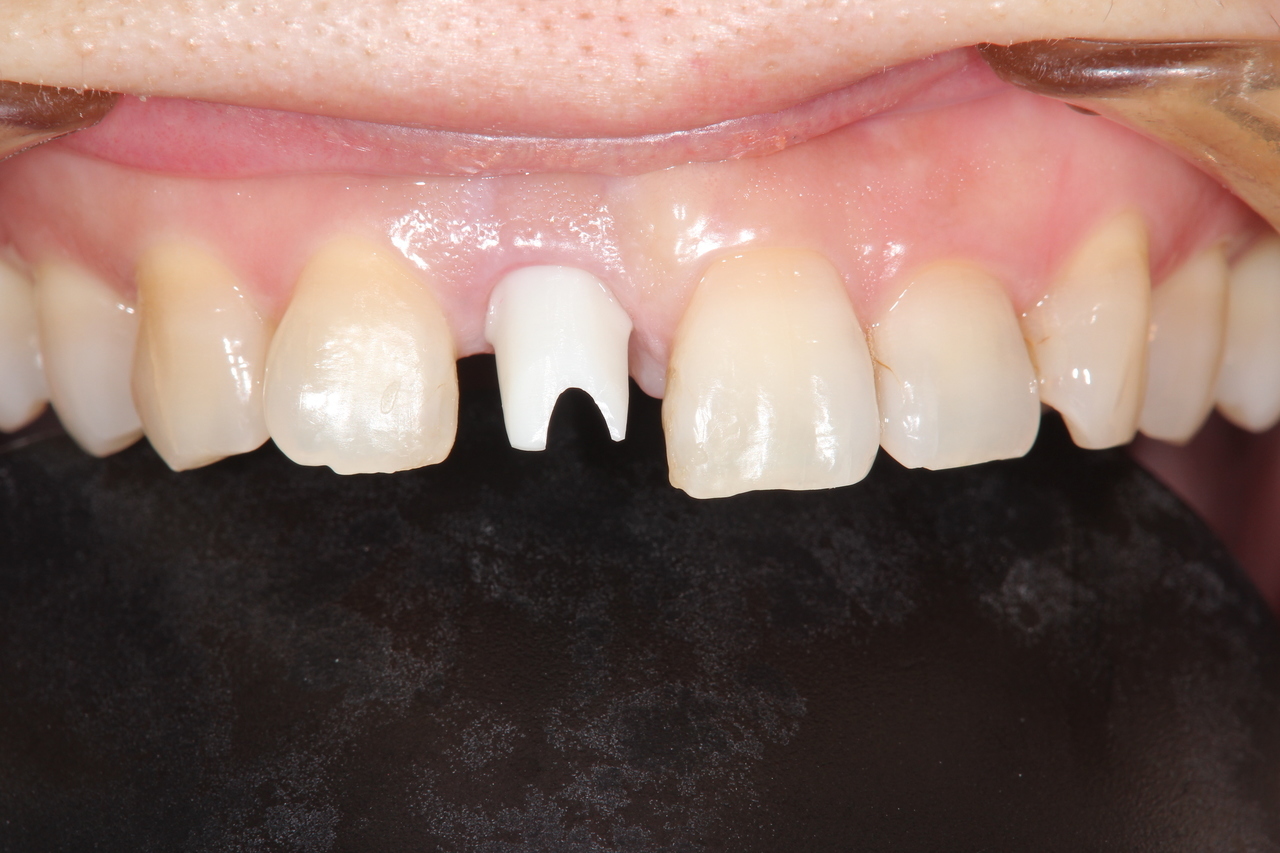

前歯インプラント(美しさを重視した場合は、ジルコニアでセメント固定がお勧めです。前歯の場合は、歯肉の形をシャープできれいな形にする為、仮歯が必要です。)

(下田市在住 女性)

治療の流れ

前歯破折

神経を取って差し歯にしていた歯根が破折したため、抜歯することになりました。

前歯インプラント土台

前歯部の審美領域は、白い土台など、より綺麗に見せるオプション費用が追加になります。

前歯インプラント

最終的な被せ物を装着すると、隣の天然歯と見分けがつかない綺麗な仕上がりになりました。

インプラント手術:250,000円

静脈内鎮静法:0円

仮歯:50.000円

ジルコニアアバットメント:120,000円

前歯用プレミアムジルコニア:150,000円

総額:570,000円+税